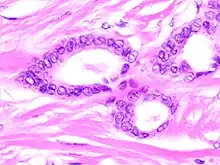

Tubular carcinomas are generally around 1 cm. or smaller, and are made up of tubules. They are usually low-grade.[2] Elastosis has been noted as common but is not present in all cases.[11]

- 1 2 Image by Mikael Häggström, MD. Reference for typical features: Pragya Virendrakumar Jain, M.D., Julie M. Jorns, M.D. "Breast - Other invasive carcinoma subtypes, WHO classified - Tubular". Pathology Outlines.

A highly differentiated invasive carcinoma that forms well-defined tubules (containing epithelium, but no myoepithelium) and that have abundant desmoplastic fibrous stromal reaction between the tubules.